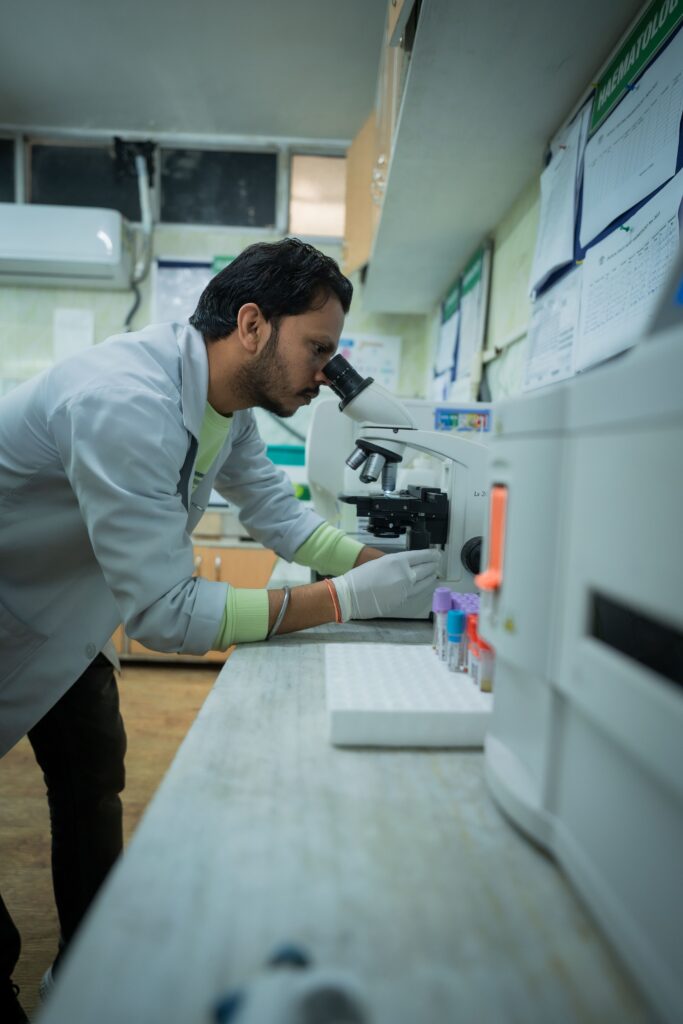

Pathology

Microbiology

Sanjeevani Multicare Hospital Gallery

Delivering the best possible treatment is something that Sanjeevani Multicare Hospital is passionate about. Whether it’s the best medical professionals, cutting-edge equipment, cutting-edge facilities, or smiling nursing staff, we think that what makes us even more outstanding is our character, the way we treat our patients as if they are our family members and friends and with the highest respect and care.

The Sanjeevani Multicare Hospital is a landmark healthcare service Institution that enjoys a unique reputation of being a popular destination for both Indian and International patients seeking treatment at an affordable cost.

Sanjeevani Multicare Hospital is the Best hospital in Amritsar, Punjab offering each patient the superior care, outstanding service, and compassion we would want for our loved ones. we also strives to lead the evolution of healthcare so that every member of the communities it serves can live a better, healthier life.